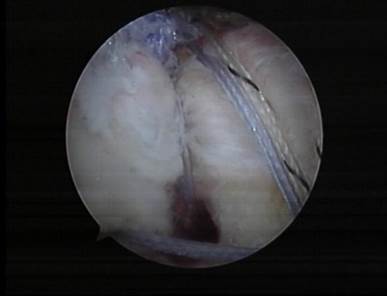

肩关节镜下修复Bankart损伤